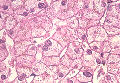

- 小葉構造;保持されている

- 門脈域;線維性拡大なし、単核球主体の炎症性細胞浸潤が軽度、1カ所の門脈域にセロイド・リポフスチノーシス小葉間胆管および脈管の異常所見なし、細胆管の増生

- 実質域;巣状壊死が少数、実質内の細線維の伸長あり(1カ所)、核の偏在、胞体内の淡染性の物質(部分的にはGround-glass 様変化)とビリルビン色素顆粒、核空胞化、類洞内への好中球浸潤を軽度にみる、偽腺管様構造、肝細胞および核の大小不同、削り取り壊死は認めず

病理組織診断;Parenchymal damage (minimal change) with bile stasis. (Drug-induced liver disease, compatible with)